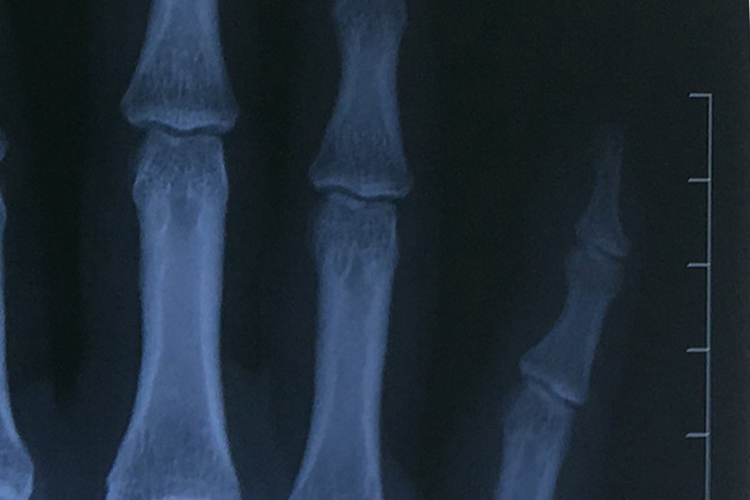

小手指错位通常为小指关节脱位,可通过手法复位后进行固定,并配合药物治疗,以促进恢复。恢复过程中需通过X光片确认关节和两侧骨骼位置的恢复情况,最初可见关节明显脱位,两侧指骨不对应;固定时可见关节两侧骨骼恢复正常位置;恢复后可见关节两侧骨骼在去除固定后,仍然维持正常位置,关节形态恢复正常。

小手指错位早期应重视其他手指的功能训练,但切忌触摸、捏揉、摇晃该关节,以免发生增生及粘连,导致肿胀长期不消并遗留功能障碍。去除固定后,可做患指的掌指关节和指间关节的主动伸屈活动,活动范围由小到大,逐渐进行,促进恢复正常功能。